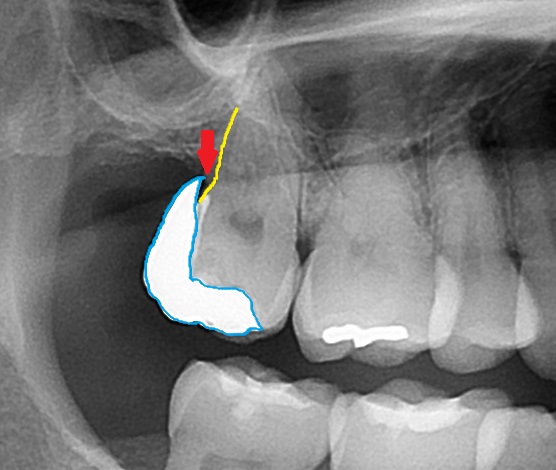

しかし、これは絶対に悪いとも言い切れません。なぜかというと、その歯に過大な力がかかった時に代償として割れてくれる場合もあります。壊れない材料を使うという事は、材料は壊れなくても、歯が壊れる可能性があるという事です。材料が割れた場合は、まだ替えがききますが、歯が割れてしまった場合は、最悪の場合は抜歯になるかもしれません。

☝残った歯に亀裂がはしっている。(ヒビが入って割れている)